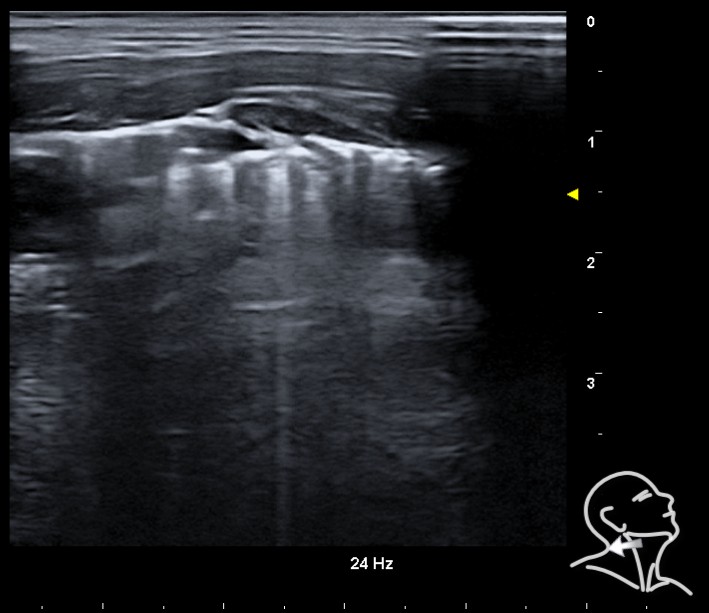

En región cervical y torácica bilateral, inferior a la fascia cervical, se observan puntos hiperecogénicos con artefacto en cola de cometa, compatibles con líneas “E”. En hemitórax izquierdo, ausencia de deslizamiento pleural y de líneas “B” y signo del código de barras, aunque no es posible visualizar el punto pulmomar.